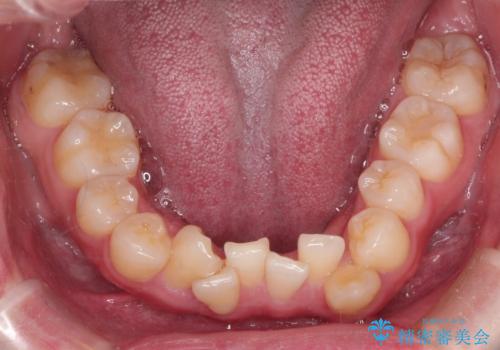

【重度叢生ワイヤー矯正】きれいな歯並びにしたい

- きれいな歯並びにしたいとの希望を持って来院された患者様です。

上下左右小臼歯を抜歯する治療計画を立て審美装置にて治療を行いました。

骨格的3級傾向もあり、咬合関係を仕上げるのに時間がかかりましたが、患者様には大変満足していただけました。